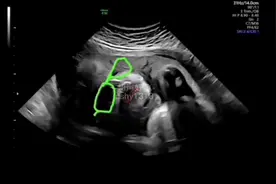

孕12周:初次见面

这时候会进行NT的检查,看看胎儿颈后透明层筛查有没有畸形的风险。